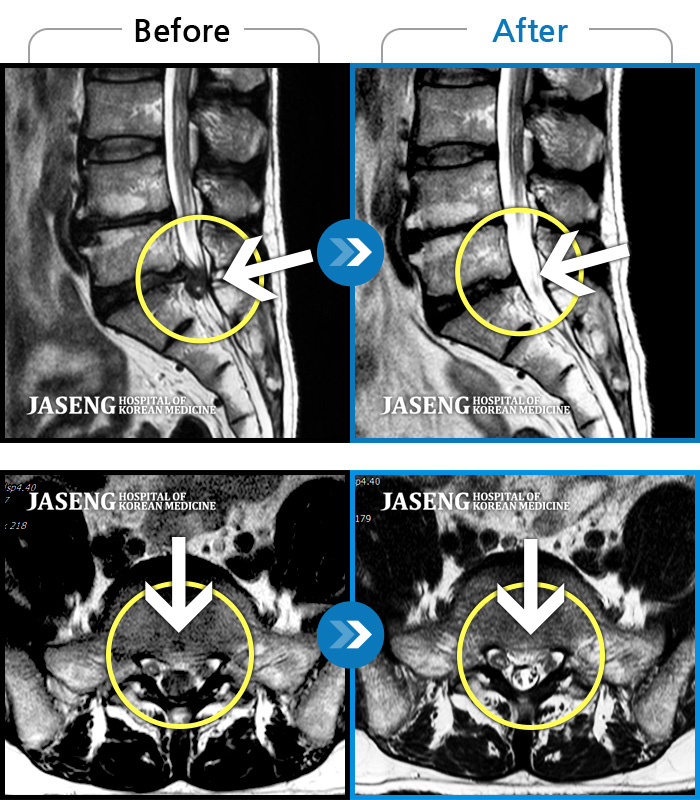

허리디스크

강남 · 강만호 원장

허리 통증 및 왼쪽 다리 근력저하 감각저하로 일상생활이 불가능했습니다.

촬영시기

2024.05.18 ~ 2025.12.03

2025.12.19

조회수 101